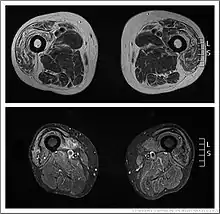

Inclusion body myositis MRI

Muscle imaging can help establish the pattern of muscle involvement and selection of a biopsy site.[1]